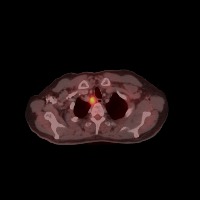

Diagnostic Aid in Medical Imaging: Radiologists could use this model to identify and characterize lymph node tumors in CT scans, assisting in early detection and diagnosis of potential cancerous growths.

Medical Research: Researchers might employ the model to study the characteristics and progressions of various types of lymph node tumors, towards producing more effective treatments and prevention strategies.

Training Medical Students: This model could serve as an invaluable tool for training medical students or residents in radiology, allowing them to familiarize themselves with the appearance and location of different lymph nodes, as well as to recognize varied tumor classifications.

Telemedicine: In remote or rural areas lacking immediate access to expert radiologists, this model can come handy as it assists primary care providers or mid-level practitioners in identifying lymph node tumors and making more effective referrals.

Second Opinion: Patients with possible lymph node tumors might use the model as a 'second opinion' to verify diagnoses, ensuring there are no oversights in their scans.